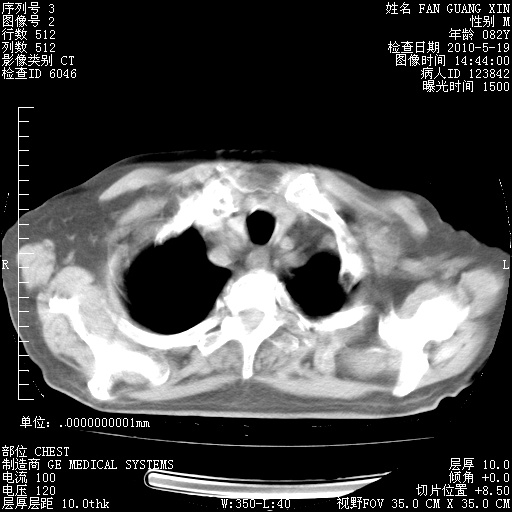

复查肺部CT,明显好转。为什么发热呢?

治疗3周后的肺部CT